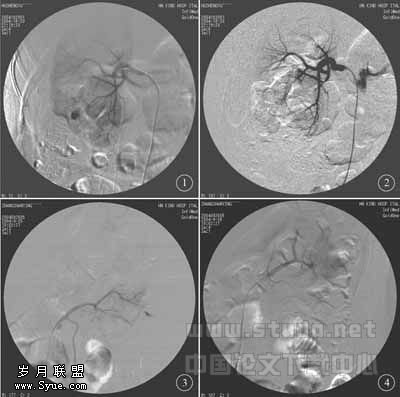

例1,患者, 男,54岁,9天前在外院行右PCNL术,右肾出血不止,药物止血无效。查:右肾造瘘管持续流出深红色尿液,导尿管持续流出淡红色液体。Hb 86g/L,RBC 3.0×1012 /L。经皮股动脉穿刺插管至右肾动脉主干行DSA检查,示右肾下前段动脉中部有一1.0cm×1.0cm大小团状外溢造影剂影,换4F Cobra管进一步超选至出血肾段动脉,注入明胶海绵颗粒和条栓塞治疗,出血点消失,造瘘管和导尿管中尿液变清,3天后拔管出院( 图1、图2 )。

例2,患者,女,37岁,左PCNL术后反复间断出血20余天,持续药物止血无效,在当地医院输血200ml,查:右肾造瘘持续流出红色液体,Hb 66g/L,RBC 2.3×1012/L,穿刺插管至左肾动脉行DSA 检查,示肾动脉后干单独起源于腹主动脉,动脉分支远侧有一约1.0cm×0.6cm大小出血点,超选至出血动脉分支用明胶海绵颗粒予以栓塞,造影复查出血点消失,造瘘管和导尿管中尿液变清,4天后拔管出院( 图3、图4 )。

图1 右肾下前段动脉分支远侧有一1.0cm×1.0cm大小团状外溢造影剂影(肾出血) 图2 以4F Cobra管超选至出血肾动脉分支远侧,注入明胶海绵颗粒和条栓塞治疗后主干肾动脉DSA检查,肾出血消失 图3 左肾动脉后干单独起源于腹主动脉,DSA检查示后段动脉分支远侧有一约1.0cm×0.6cm大小出血点 图4 超选至出血动脉分支后用明胶海绵颗粒栓塞,出血点消失